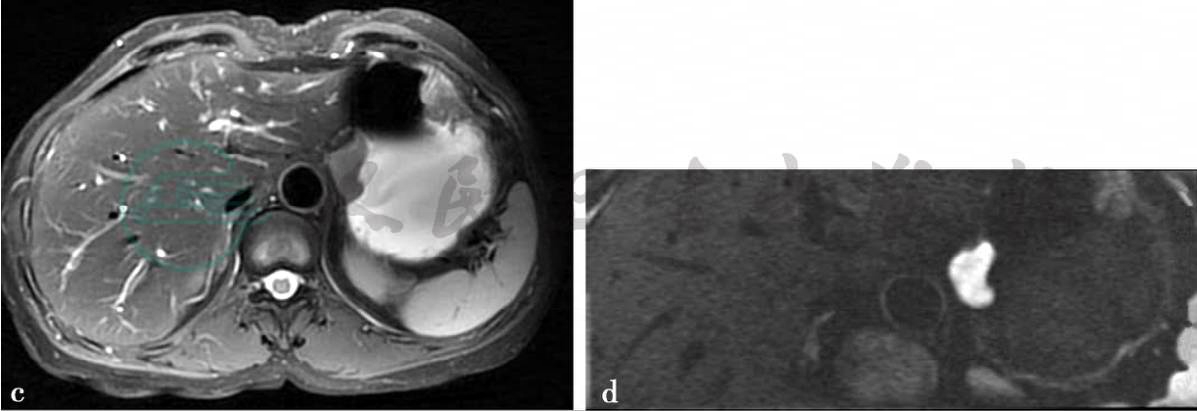

病例7:CT增强扫描及MRI平扫及弥散加权图(贲门胃底癌)。

图1 图1a,CT增强静脉期图。图1b~d,分别为轴位T1WI,T2WI及DWI图。贲门胃底可见软组织肿块,轻度强化,MRI上呈稍长T1,稍长T2信号,DWI上为高信号